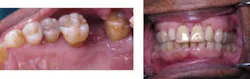

Miss Novice after the LANAP protocol.

Miss Novice showed radiographic evidence of bone regeneration seven months post LANAP. She completed orthodontics and shows stable bone three years post LANAP.